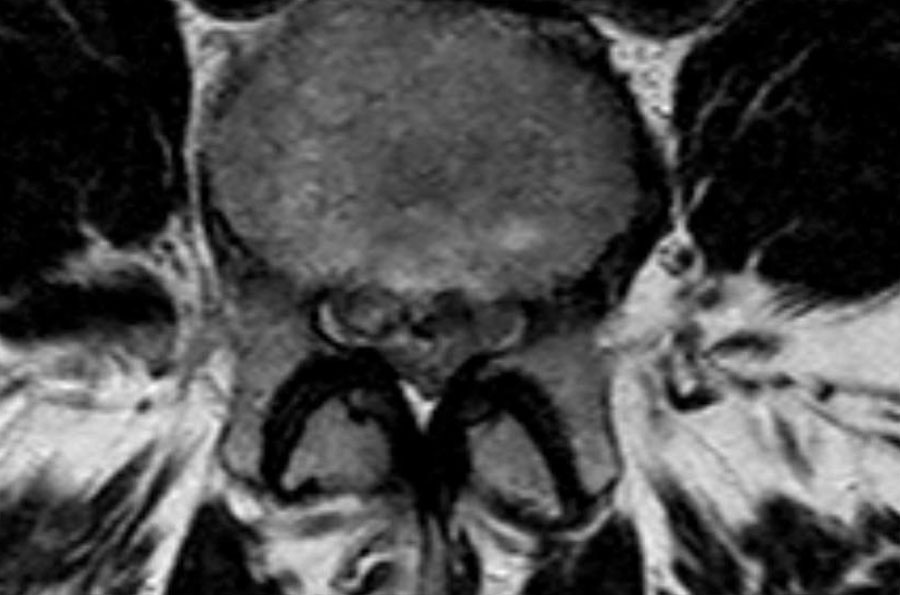

Cuộn qua các hình ảnh để quan sát đường đi của các rễ thần kinh tại mức độ đĩa đệm, ngách bên, lỗ liên hợp và ngoài lỗ liên hợp.

Tại mỗi mức độ có thể thấy các bệnh lý đặc trưng, nhưng có sự chồng lấp đáng kể.

- Tại mức này, có hẹp ống sống nặng do phình đĩa đệm và thoái hóa khớp mỏm khớp.

Ngoài ra còn có rách vòng sợi (tăng tín hiệu) là nơi đĩa đệm thoát vị qua (mũi tên vàng). - Tại mức ngách bên, có thoát vị khu trú của chất đĩa đệm gây chèn ép rễ thần kinh L5 (mũi tên vàng).